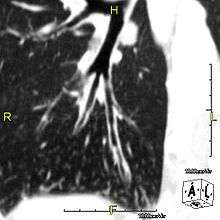

| Normal cilia (A) and cilia representative of Kartagener's syndrome (B). | |